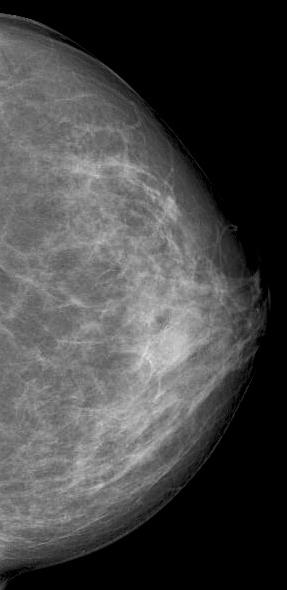

Diagnostic mammography showed scattered fibroglandular densities

Right breast showed in retroareolar region, an equal density oval mass with partially circumscribed margins measuring 6.6x5.2 cm. There were no associated suspicious calcifications. Right axilla showed a round dense LN of 1 cm.

Mammographic features include focal or global asymmetry, irregular focal mass, skin thickening with edema or trabecular thickening, asymmetric increased breast density and axillary lymphadenopathy. It can rarely present as a circumscribed mass or architectural distortion. Calcifications are very rare. Mammogram will be normal in about 8-45% of the cases in the setting of heterogeneously and extremely dense fibroglandular tissue.